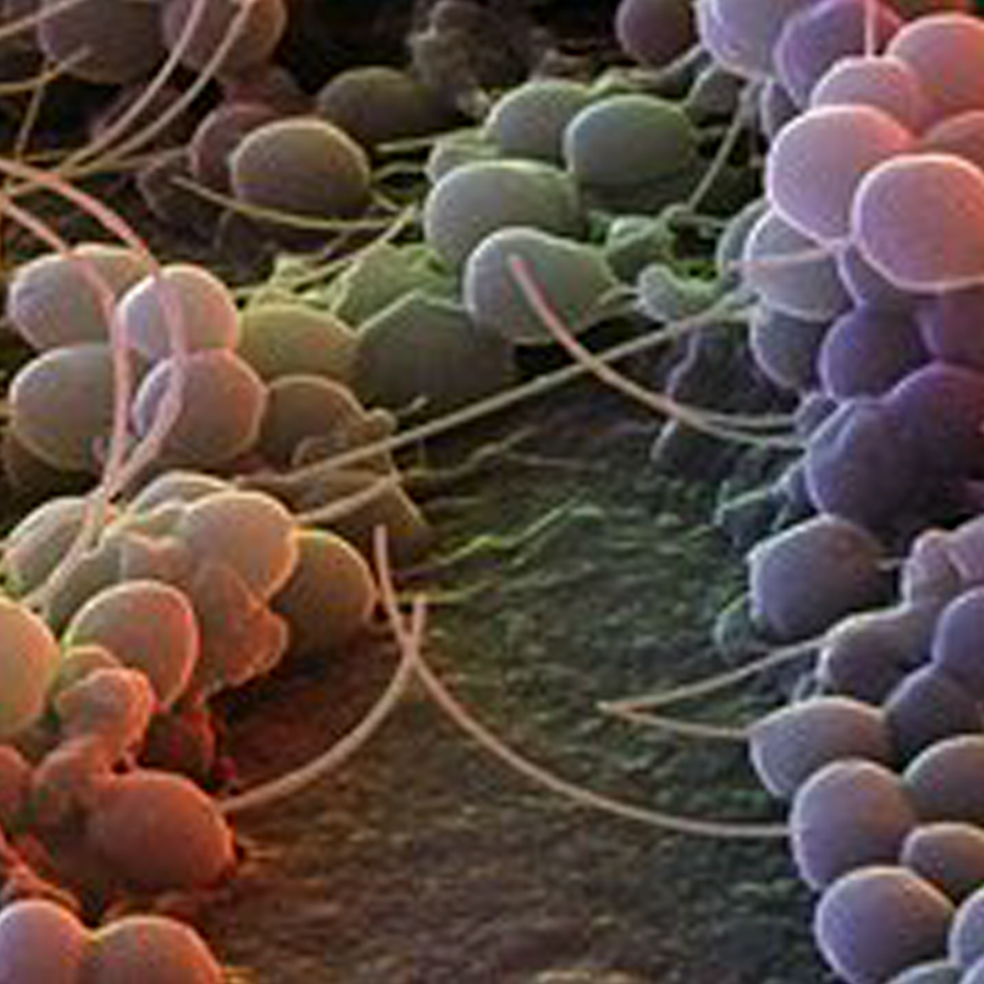

Ácaros del género Demodex, minúsculos artrópodos alargados con patas rechonchas, habitan en los folículos capilares de frente, cejas y pestañas, donde se alimentan de sebo. A veces abandonan estos confortables lugares para dar un paseo nocturno por la cara. Aumentan con la edad: casi todos los ancianos los tienen.